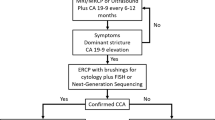

At present, there are no effective screening protocols for early detection of sporadic CCA, nor explicit recommendations for screening of PSC patients for CCA. The most effective strategy for detecting early CCA in PSC involves annual magnetic resonance imaging (MRI) and magnetic resonance cholangiopancreatography (MRCP) or ultrasound and CA 19-9, followed by endoscopic retrograde cholangiopancreatography (ERCP) and brush cytology or forceps biopsy for evaluation of suspicious strictures [8]. This strategy, however, is invasive and costly [9]. The only curative modality for CCA is surgical resection or liver transplantation for early-stage disease [10]. The vast majority of patients with CCA have late-stage disease not amenable to surgical resection with curative intent [11]. The standard of care for intermediate to advanced stage CCA, which is chemotherapy, is typically accompanied by significant toxicity and a high rate of recurrence. In this chapter, we provide a detailed review of the current practices employed to evaluate and manage patients diagnosed with CCA, with a particular emphasis on the imaging features.